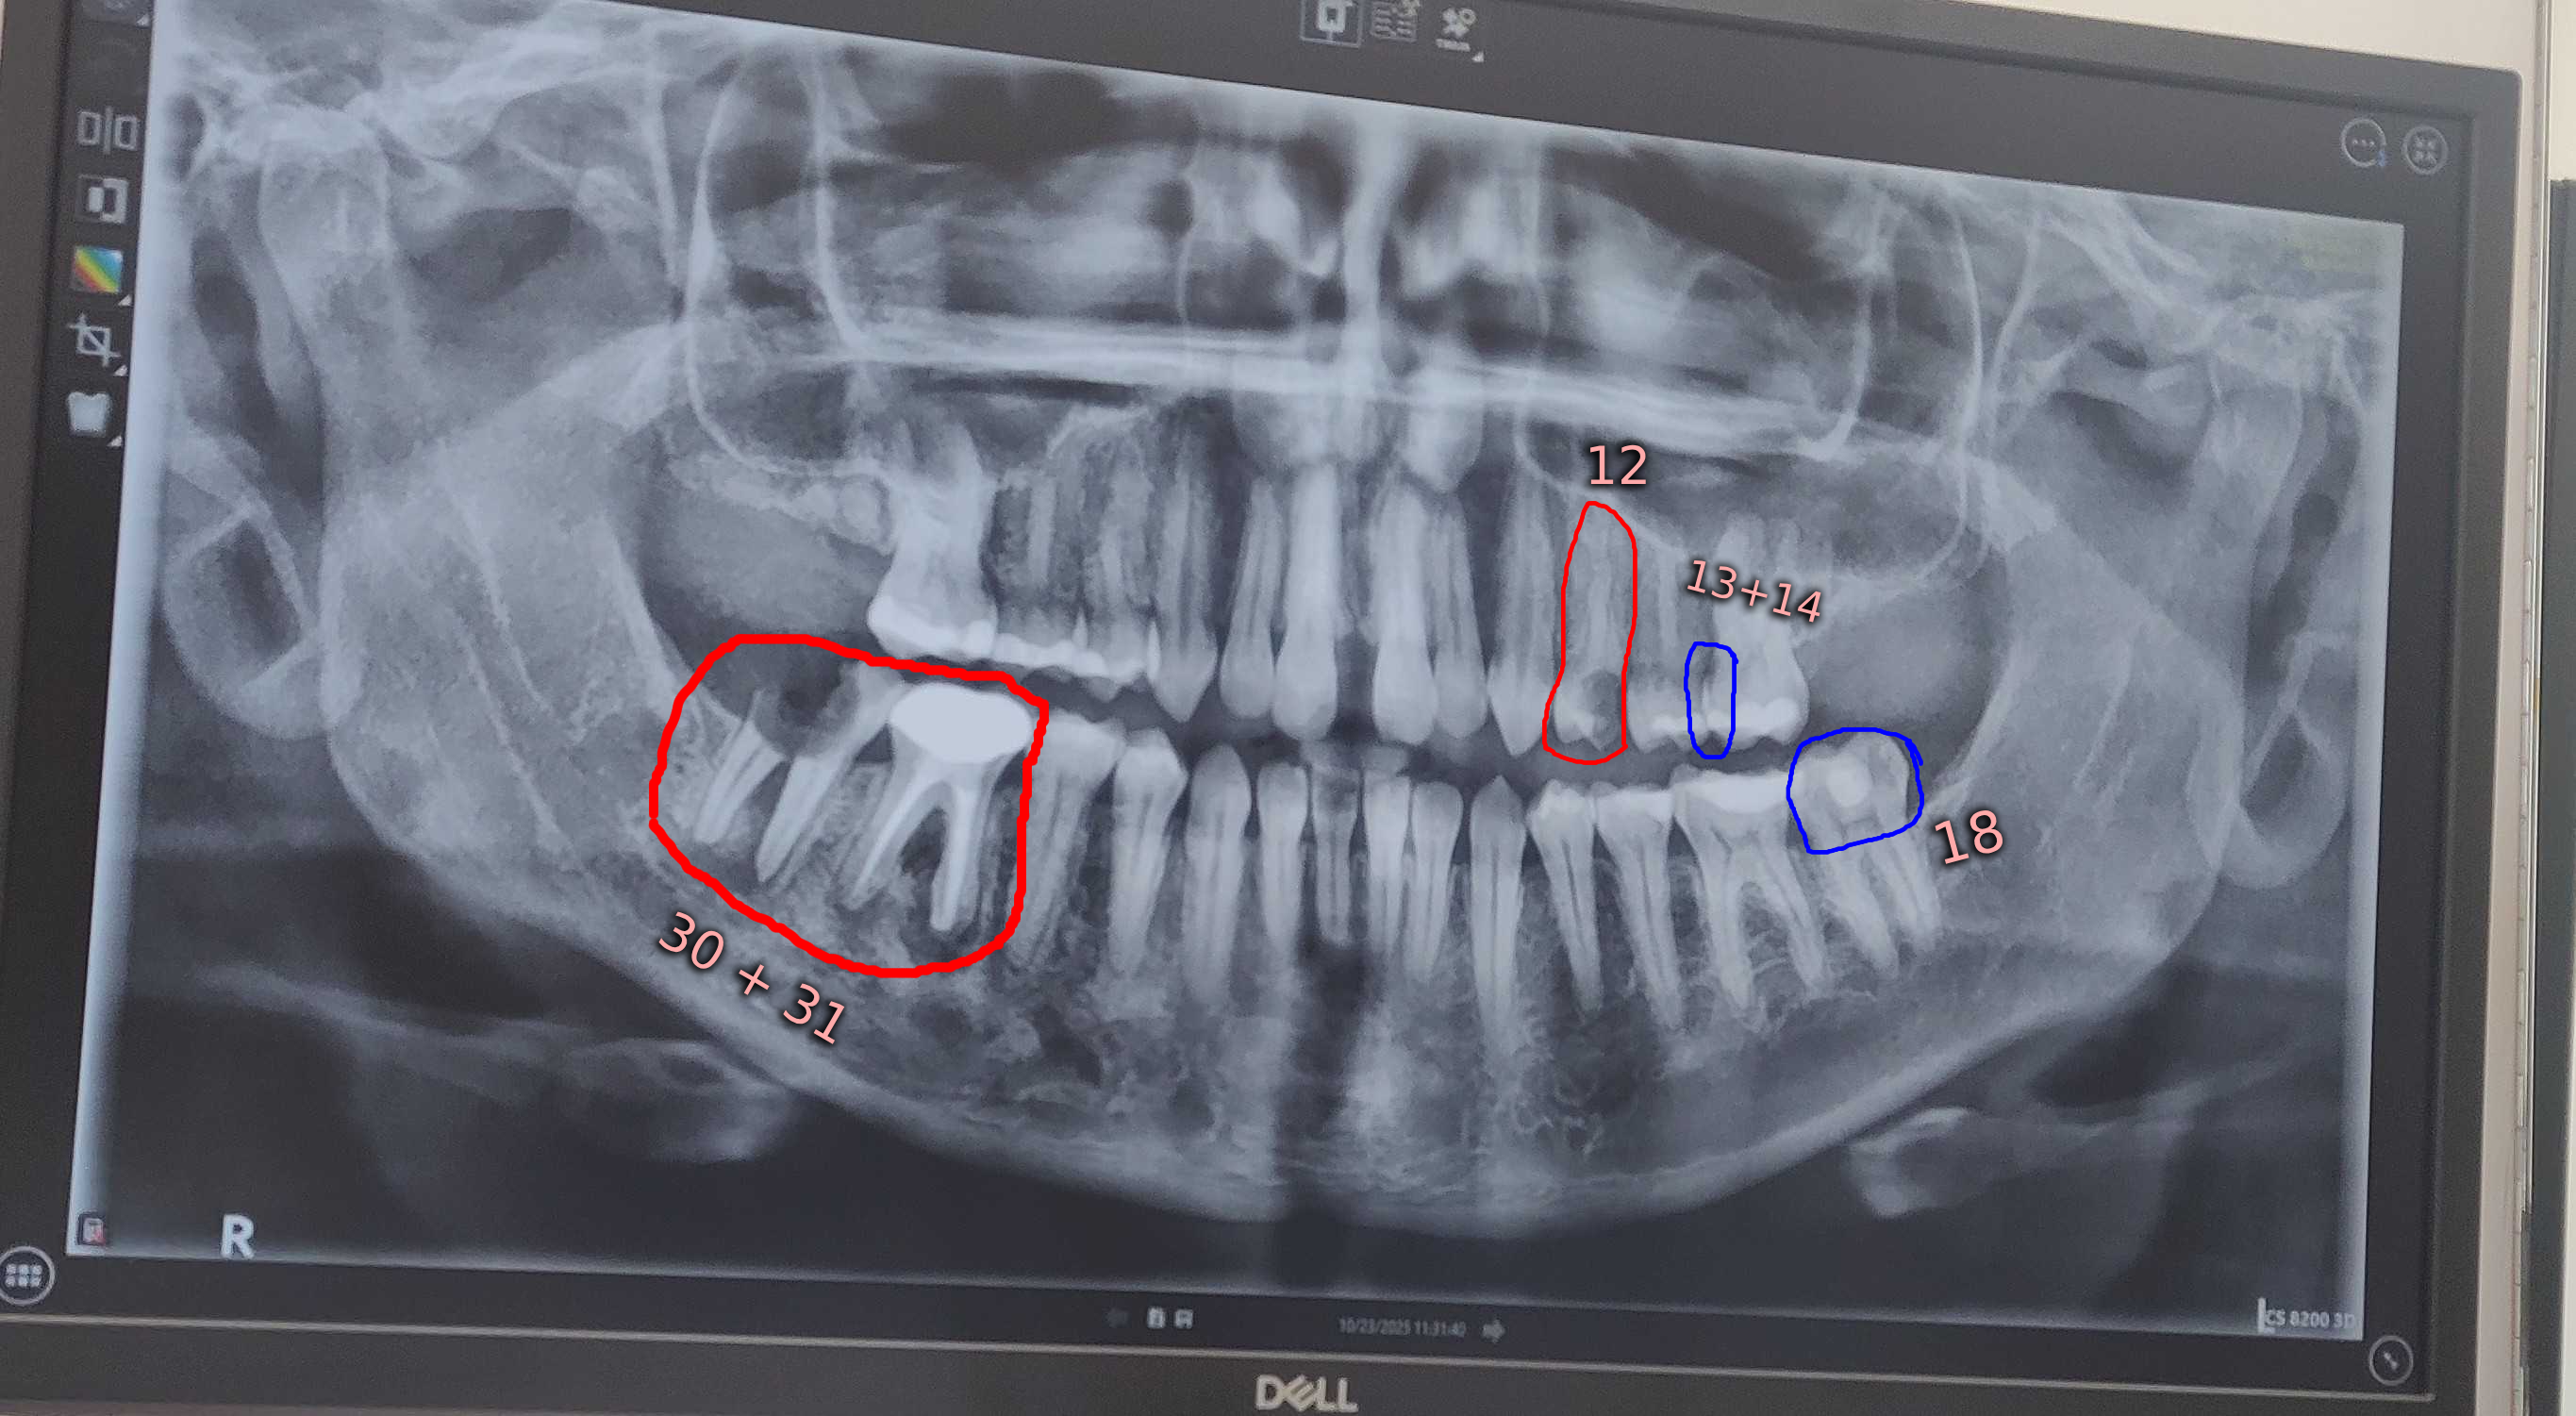

Two weeks ago, part of my back molar broke off. you can see it in the x-ray; the one that's just the roots pretty much. I had a dental appointment this past week where we discovered several pressing issues and decided different treatment options with the original cost for everything being only around $17,200USD.

However, the day after my exam, the majority of one of my front tooth (12) that I had plans to save, broke off.

In my photos, I have included the original bill for each part of the treatment plan. I'm unsure how they'll want to handle the newly ruptured tooth, but they had already suggested extraction before it was ruptured like this. It is likely that it will need to be removed and have a bone graft as well. My changes to the bill total are my own math, based on their prices included for extraction, bone graft, and implants, for the newly ruptured tooth.

Each part of this process will be expensive as you can see. But, each part can be done in different times. At the moment, getting the implants is not a primary concern. They are something I would genuinely like to do, but I want to focus on the core health issues. Which is the removal and bone graft of the teeth circled in red and the fixing of the teeth circled in blue.